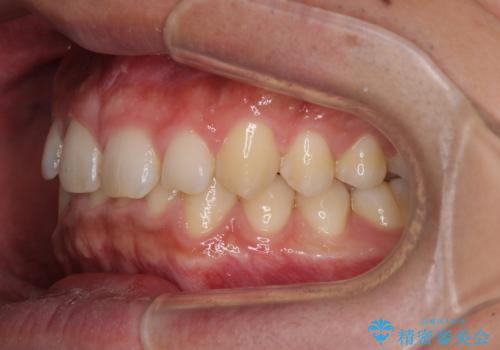

深い咬み合わせと隙間の空いた歯列をワイヤー矯正で改善

- 前歯の隙間と深い咬み合わせを改善したいとのことで来院された患者様です。

奥歯の咬み合わせは理想的な状態であったため、ワイヤー矯正でもインビザラインでも比較的容易に対応可能でした。